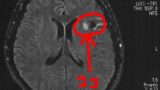

• びまん性星細胞腫グレード2(悪性転化しやすい腫瘍)

• 特に進展はなし

• 画像をもらうのを忘れた